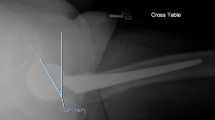

The surgical setup follows that described in Murphy et al. [13]. In summary, prior to the start of the surgery, a Polaris optical tracking system (Northern Digital Inc., Waterloo, Canada) was set up on the contralateral side. During surgery, the surgical assistant performed a pivot calibration of the optically tracked pointer. The surgeon performed the opening and initial approach as described in [7]. In addition, on the contralateral side, two small incisions were made on the iliac crest, and the base of the removable reference geometry (BrainLab, Feldkirchen, Germany) was fixated with two screws. The reference geometry establishes a fixed reference allowing the tracking of the fragment. Before the iliac osteotomy, the pelvis surface model was registered to the patient anatomy. An initial registration was established by touching the anterior superior iliac spine on the operative and contralateral side and the anterior inferior iliac spine on the operative side with the pointer. After collecting surface points on the ilium, pubis, and the iliac crest, a point to surface registration was performed [26]. Before the final osteotomy, four small indentations, referred to as fiducials, were created in an approximately square pattern on the intra-operatively planned fragment using a 1 mm bone burr. The initial position of the fragment was recorded by touching the fiducials with the pointing device. The final osteotomy was completed, and the surgeon re-oriented the fragment under fluoroscopic guidance. As noted above, the BGS-optimized surgical plan was not used during reorientation. When satisfied with the final positioning, the fragment was fixated by the use of two cannulated screws and the final position was recorded by touching the fiducials again in the same order. Validation of the BGS system was performed and was previously reported by Murphy et al. [13, 27]. The procedure for this study was practiced on six cadavers prior to patient inclusion by the operating surgeon and surgical team to reduce the learning curve and establish an efficient workflow. The intra-operative workflow is shown in Fig. 2.

A schematic overview of the intra-operative workflow. First, the registration between the model and patient is performed by matching the anterior superior iliac spine on the operative and contralateral side and the anterior inferior iliac spine on the operative side with manually selected points on the model (blue and green numbers). After collecting surface points (green points) on the ilium, pubis, and the iliac crest, a point to surface registration was performed to refine the registration. Subsequently four fiducial points (red numbers) are digitized on the planned fragment. Measurements of the position of the fragment and the corresponding angle measurements can then be determined by digitizing the fiducial points